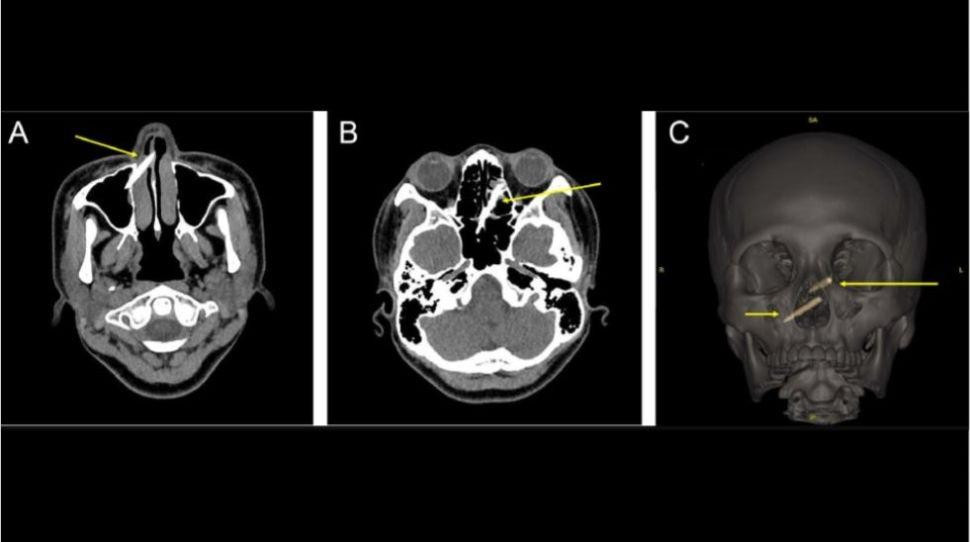

Mảnh đũa lọt vào xoang mũi

Một người phụ nữ ở Đài Loan, 29 tuổi, đánh nhau dữ dội với em gái trong bữa ăn bằng chiếc đũa trên bàn và bị mảnh vỡ của chiếc đũa văng vào xoang trong một tuần mà không hề hay biết. Khi thấy khó chịu, cô đi khám và chụp X-quang hai lần mới phát hiện ra hai mảnh vụn của đũa (3,5 cm và 5cm) xuyên vào vách ngăn mũi của cô. Cô đã được phẫu thuật để gắp mảnh vụn đó ra và không gặp biến chứng phẫu thuật nào.